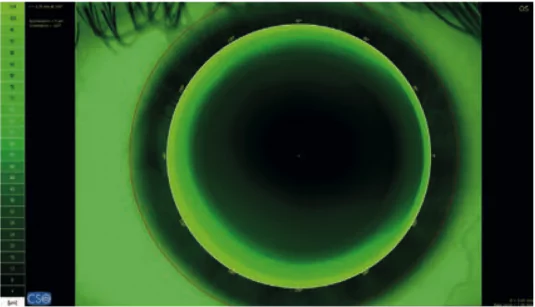

Grazie alla tecnologia Placido è possibile misurare il tempo di rottura del film lacrimale in modo non invasivo. Il sistema offre l’esecuzione e l’analisi automatica del NIBUT (Non Invasive Break-Up Time).

Grazie alla tecnologia Placido è possibile effettuare una misurazione non a contatto del tempo di rottura del film lacrimale. Il sistema offre un’esecuzione e un’analisi automatica del NIBUT (Non Invasive Break-Up Time).

Un modulo Autofit per la selezione e simulazione delle lenti a contatto rigide offre suggerimenti sulle possibili lenti da utilizzare. Il database comprende numerosi produttori comuni. Una sorgente di luce blu consente la visualizzazione dell’adattamento delle lenti rigide tramite fluoresceina.